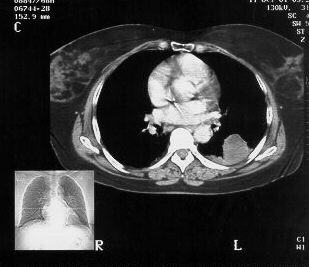

Chest CT demonstrating the 10.0cm x 6.0cm mass in Left lower lobe, apical segment, with pleural involvement.